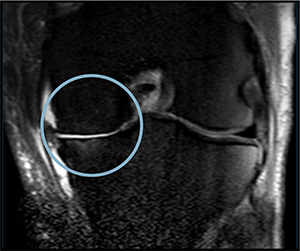

PRE TREATMENT

August 13, 2023

POST 2 APPLICATIONS

MAY 5, 2024